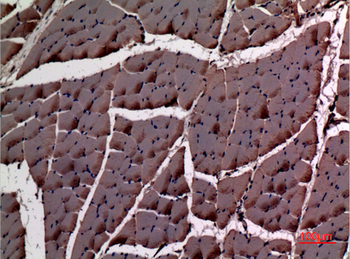

α-SMA Polyclonal Antibody

Catalog Number: orb1411650

| Catalog Number | orb1411650 |

|---|---|

| Category | Antibodies |

| Description | Rabbit polyclonal antibody to α-SMA. |

| Clonality | Polyclonal |

| Species/Host | Rabbit |

| Conjugation | Unconjugated |

| Reactivity | Human, Mouse, Rat |

| UniProt ID | P68133 |

| Tested applications | IHC-P, WB |

| Dilution range | WB: Western Blot: 1/500 - 1/2000. IHC-p: 1:100-300 ELISA: 1/20000. Not yet tested in other applications. |

| Storage | Maintain refrigerated at 2-8°C for up to 2 weeks. For long term storage store at -20°C in small aliquots to prevent freeze-thaw cycles |

| Alternative names | ACTA1; ACTA; Actin, alpha skeletal muscle; Alpha-a Read more... |

| Note | For research use only |